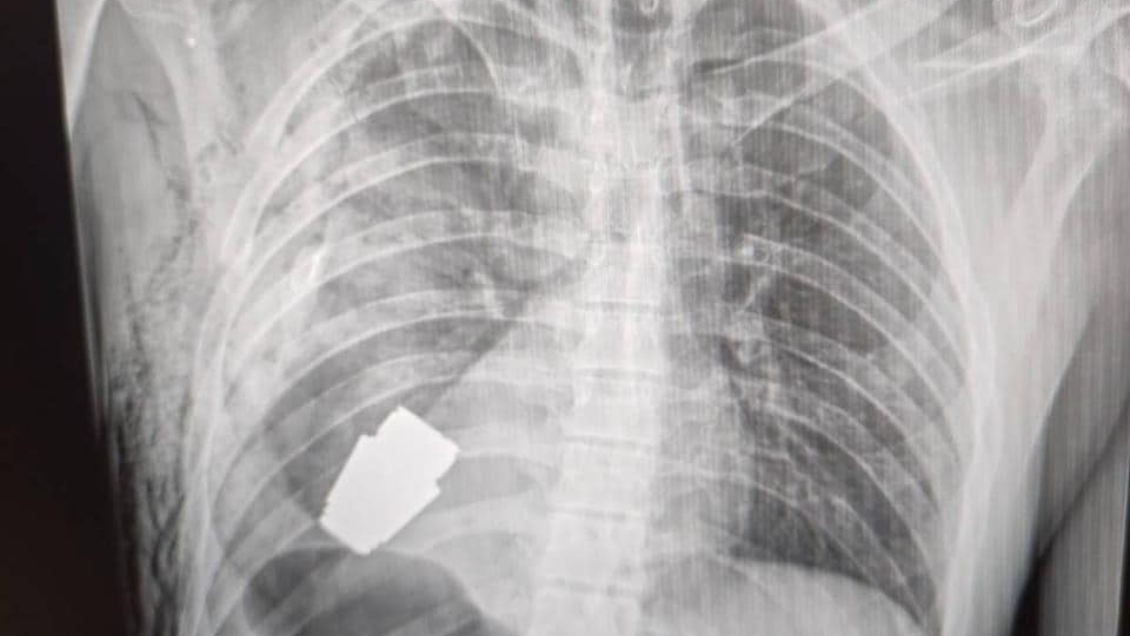

Médicos extrajeron una granada sin explotar del pecho de un soldado ucraniano

La cirugía se realizó en presencia de dos zapadores que velaban por la seguridad de los profesionales de salud.

Médicos de las Fuerzas Armadas de Ucrania